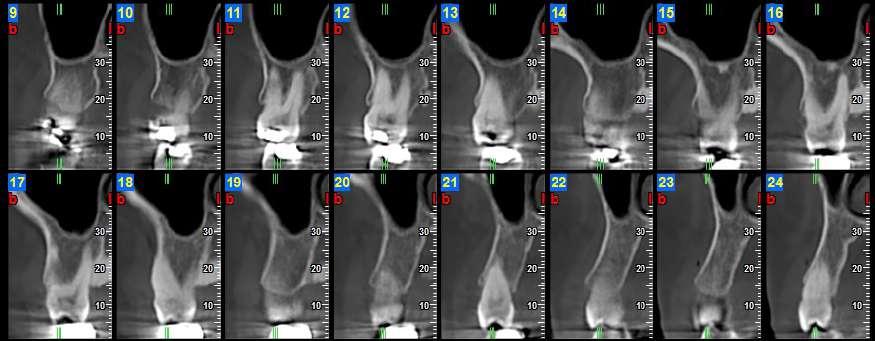

12.00 L’in uenza del genere nell’espansione scheletrica del palato, valutazione CBCT dello stadio di ossi cazione della sutura palatina mediana

Federica Altieri, Martina Mezio, Michele Cassetta